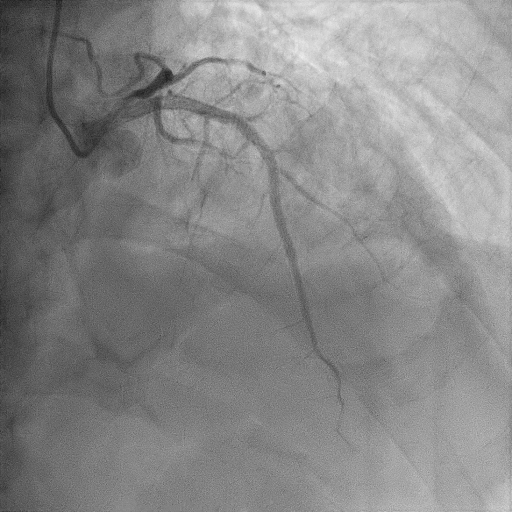

Relevant Catheterization Findings

We proceeded with delayed selective PCI to the left anterior descending artery (LAD). The left main coronary artery (LMCA) was engaged with guiding catheter Medtronic Launcher 6FR EBU 3.5. The PTCA guide wire Shun R (SHUNMEI Medical) crossed the lesion with ease. Besides, we wired the diagonal 1 with PT2 (Boston Scientific) to provide side branch protection. The proximal to mid segment of the LAD lesion was pre-dilated with Sapphire NC 24 PTCA balloon 3.0x15mm and inflated to 12 atm. The lesion was stented with Xience Xpedition 3.0x48mm and inflated to 10atm. The stent was post-dilated with NC Trek balloon 3.5x12mm and inflated to 14atm. Noted while retracting the balloon during post-dilatation, the guiding catheter advanced deep into the LMCA several times. Subsequently, patient became progressively hemodynamically unstable. Trial of aspiration with Genoss Extractor but no thrombus was aspirated. Intracoronary Tirofiban bolus was administered. Unfortunately, patient went into cardiorespiratory arrest and intensive resuscitation was commenced. Angiography showed severe flow-limiting type D dissection of the LMCA. We proceeded with rescue stenting of LMCA with Xience Sierra 3.5x38mm with inflation to 12atm. The stent was post-dilated with NC Euphora 4.0x8mm and inflated to 18atm. The final result was TIMI flow 3 but the stent was about 3 to 5 mm proximal to the LMCA ostium. An intra-aortic balloon pump was also inserted and patient required 4 inotropes.

Iatrogenic catheter-induced left main coronary artery dissection is a life-threatening complication. Meticulous manipulation of catheter is of upmost important during percutaneous coronary intervention to prevent such complication. Rescue percutaneous angioplasty of the LMCA dissection is potentially life-saving by restoring coronary flow and prevent further irreversible damage to the myocardium. As the stent was protruded outside the left main ostium and possibly under-expanded, the risk of stent thrombosis and technical difficulty during future PCI are high. Therefore, proper reconstruction and flaring of the stent under IVUS guidance are essential but our patient declined.